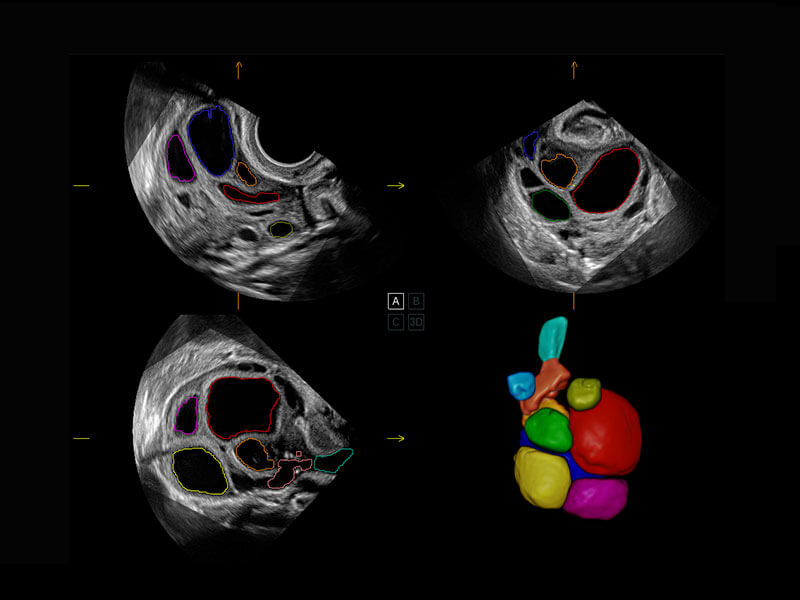

盆底超声

P60为盆底超声检查提供应用方案,多种腔内及腹部容积探头提供从二维、三维到四维的优异图像品质,实时快速三维容积数据获取,专业的测量工具包等人性化设计,为超声医生诊断提供有力保障。

Lev.Hiat A-r: 16.33 cm2

Lev.Hiat H-r: 53.70 mm

Lev.Hiat W-r: 43.96 mm

Lt-LUG-r: 24.16 mm

Rt-LUG-r: 19.94 mm

S-Pelvic

能够简化盆底检查的操作流程,可在二维模式及三维成像模式下实现一键自动提取出标准切面、自动识别当前切面、自动测量,提升盆底检查的高效性,同时也能让青年医生快捷的获得准确的检查结果。